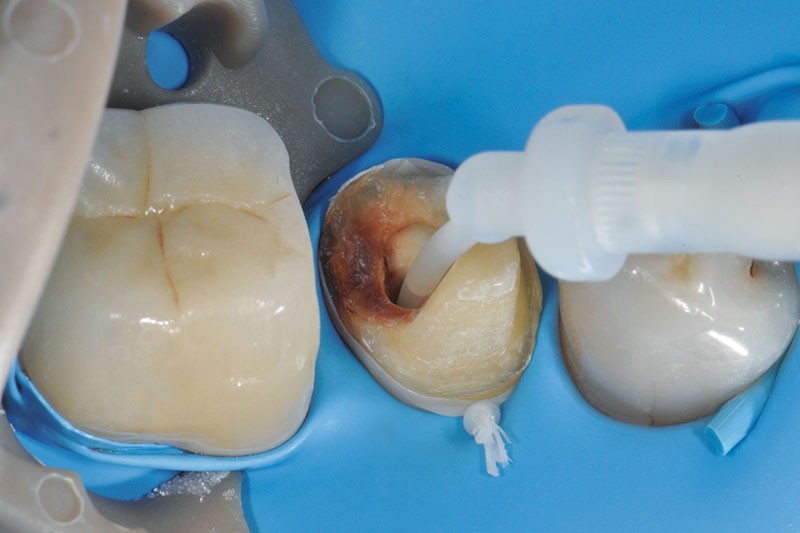

3, 4, 5. La restauration est déposée, les tissus carieux éliminés et la cavité d’accès aménagée avant la réalisation du traitement endodontique. La radiographie postopératoire permet de visualiser l’obturation du canal latéral en regard de la LIPOE.